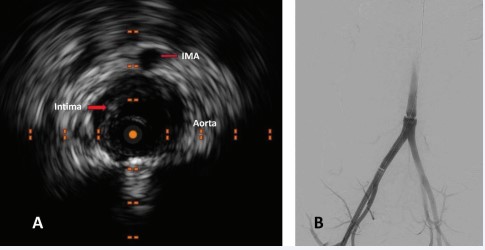

The patient is a 24-year-old male restrained driver involved in a head-on collision. He was taken to a local hospital where his primary complaints included abdominal and back pain. Computed tomography (CT) revealed a burst fracture of L3 and findings suggestive of contained transection of the abdominal aorta. Weather conditions delayed transport to a level 1 trauma center which was ultimately accomplished 4 hours later. Upon arrival, he was neurologically intact and continued to describe abdominal and back pain. He was normotensive, though slightly tachycardic. He had normal lower extremity pulse exams. He had bruising across his chest and abdomen consistent with seat belt and upper body restraints. Imaging from the referring hospital was reviewed by the trauma and vascular teams and confirmed the appearance of contained abdominal aortic transection just below the take-off of the inferior mesenteric artery (IMA) and above the bifurcation. There appeared to be a circumferential disruption of the aortic intima on CT imaging [Figure 1]. No other obvious intra-abdominal injuries were apparent.

Figure 1: Computed tomographic image of abdomen obtained upon emergency department arrival which shows circumferential transection of the intima of the abdominal aorta (arrow).